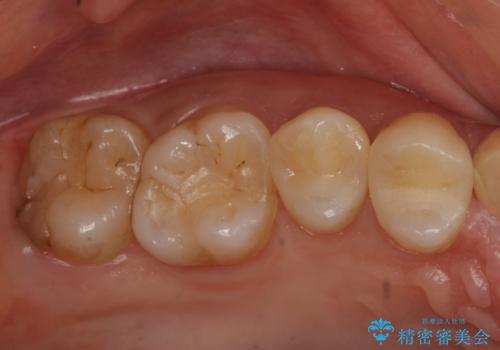

- 歯の健診にて来院。

レントゲンを撮った時にう蝕があったため、拡大鏡下でう蝕が残っていないか確認し

セラミックの詰め物(e-maxインレー)にて治療を行いました。